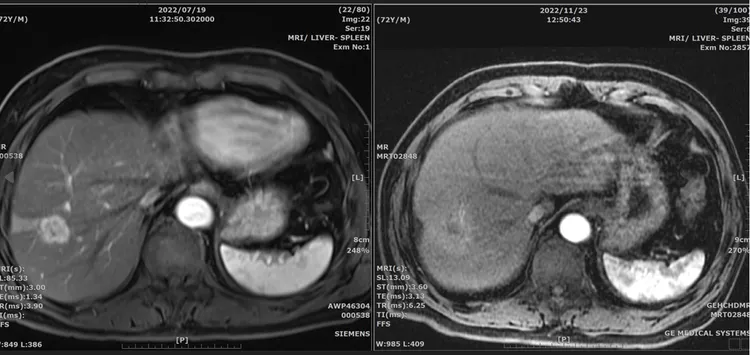

台北榮總副院長、胃腸肝膽科醫師李偉強說,童先生的腫瘤在發現時,大小約為2.6x2.3x2.6(公分),原先右肺葉的腫瘤,經評估其體能狀況等條件適合,8月經重粒子治療後,11 月已完全消失,整體而言除了皮膚表面紅紅的,並沒有其他不適症狀,且非侵入性、無痛感,整個療程共計4天,集中在1星期內完成。